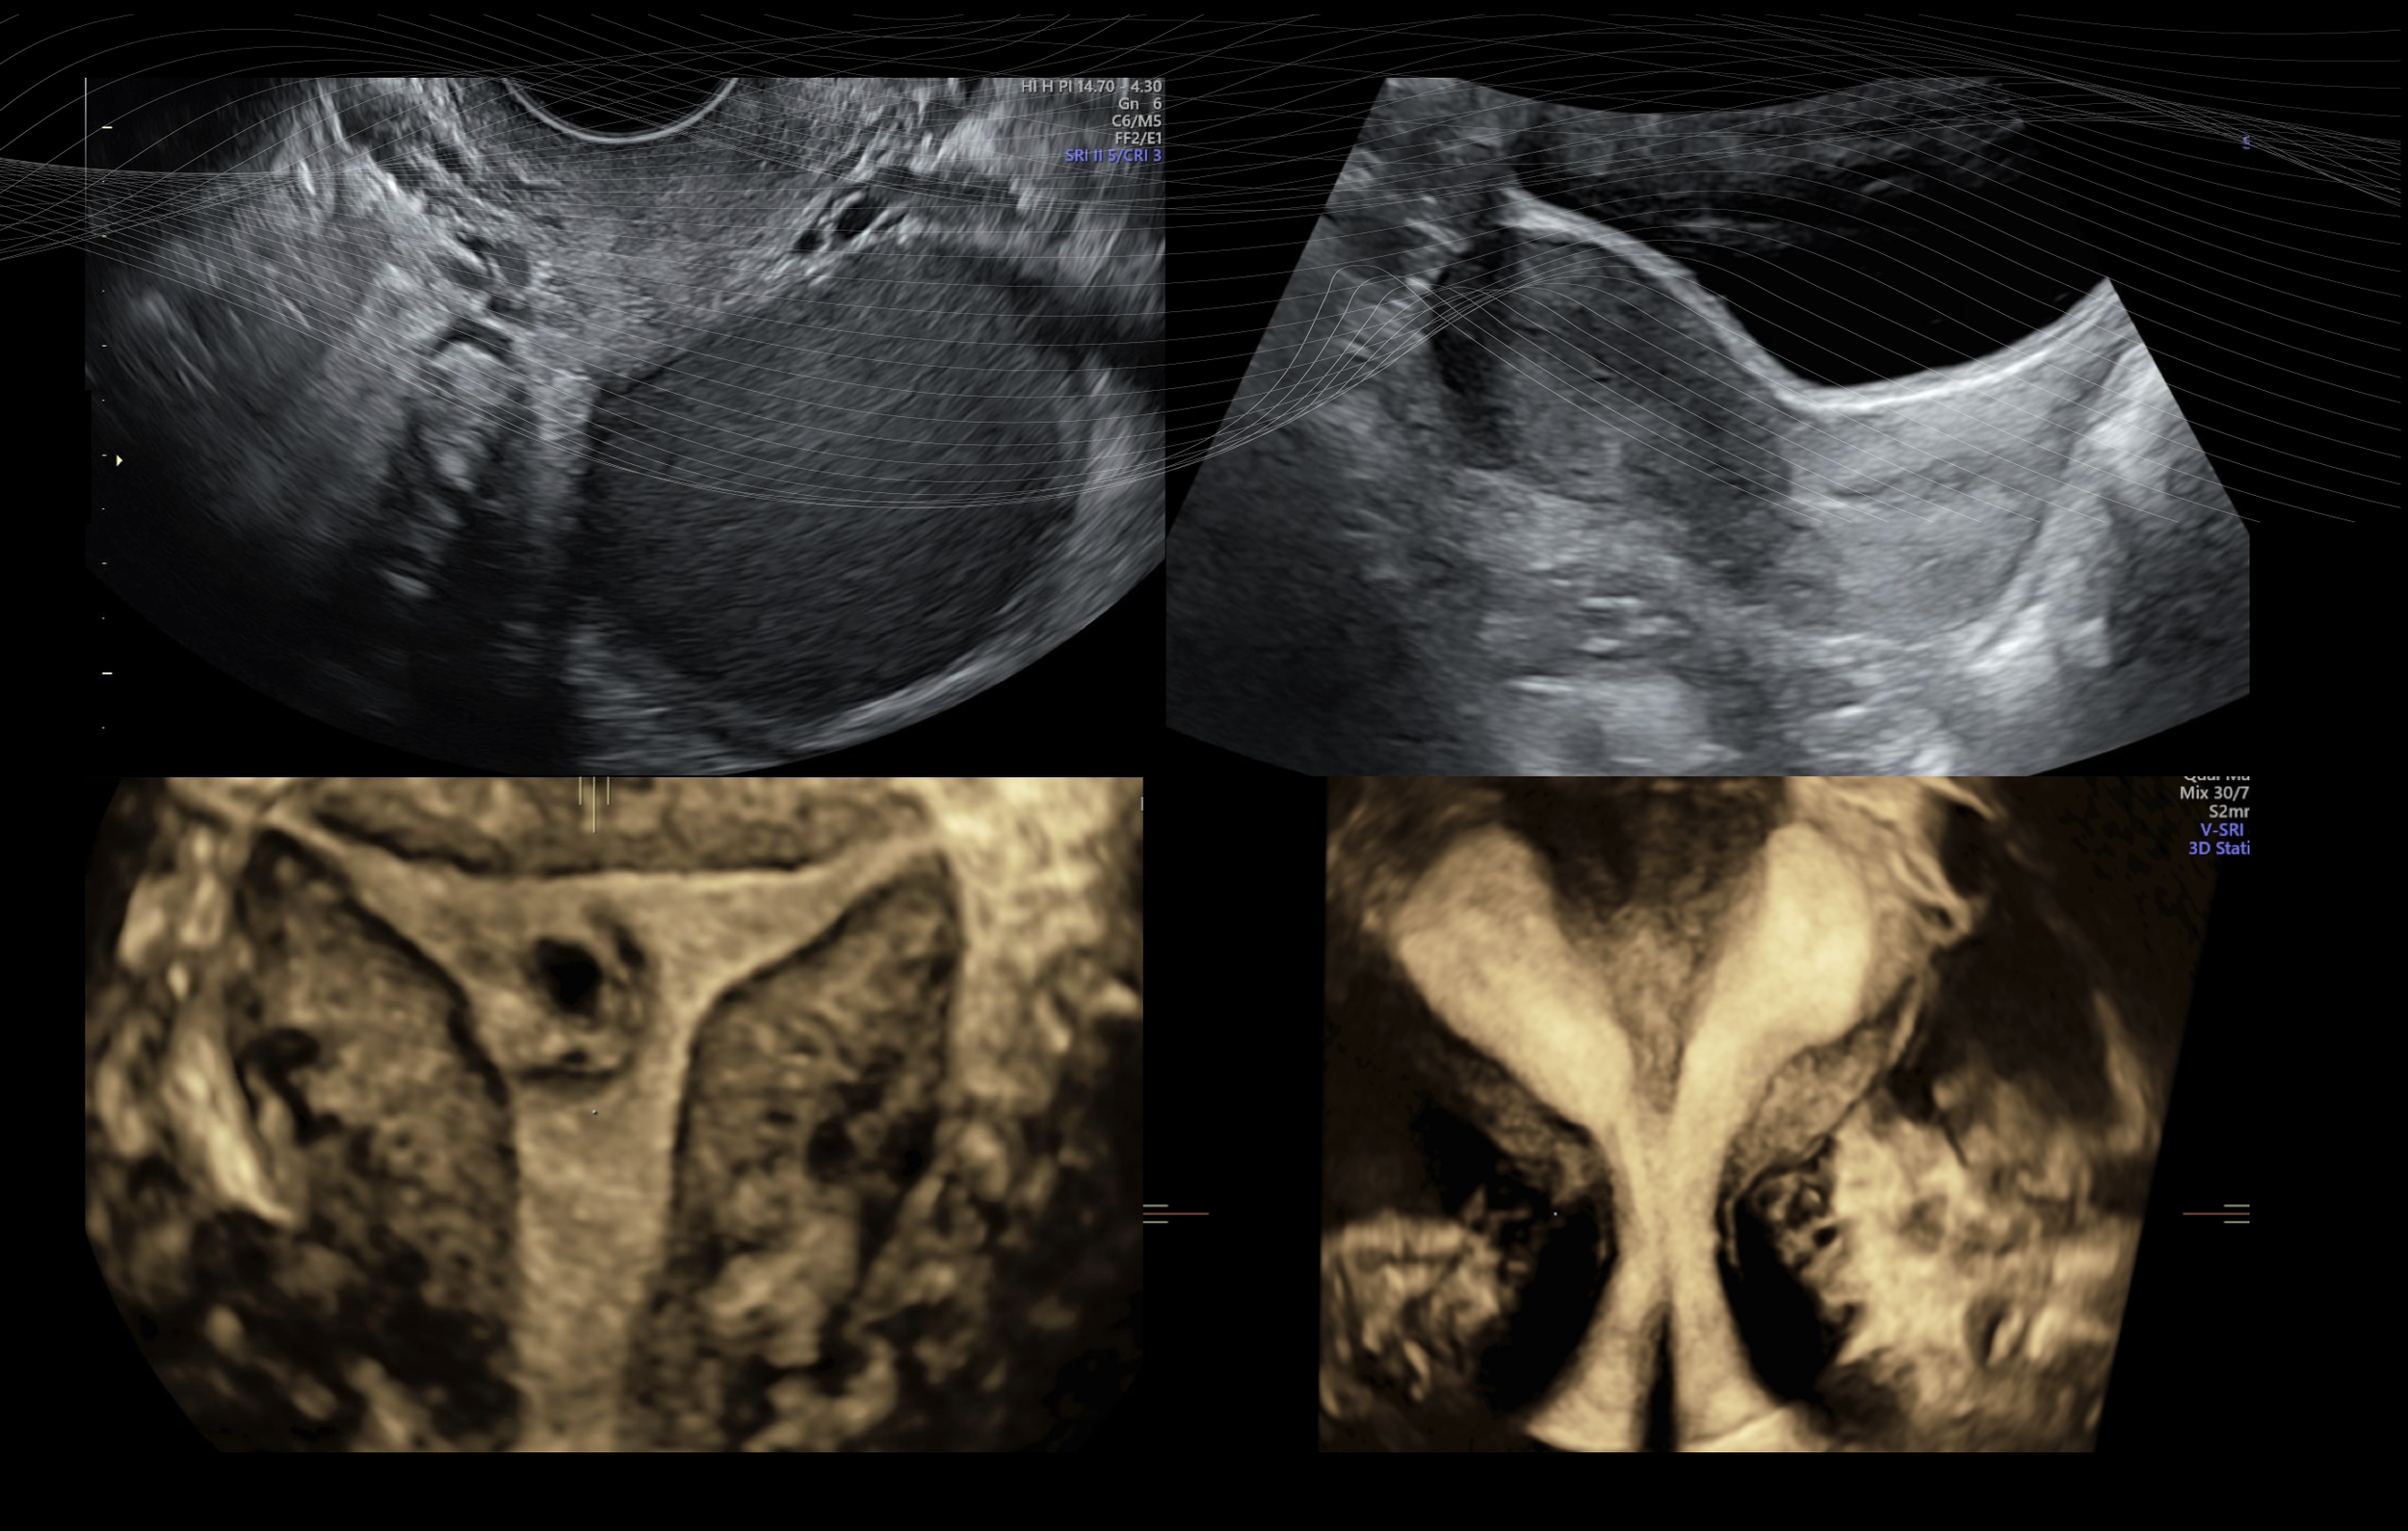

Vous proposez des échographies de qualité pour le diagnostic d’endométriose , de fibrome , de pathologies gynécologiques ou dans le cadre d’une évaluation de la fertilité .